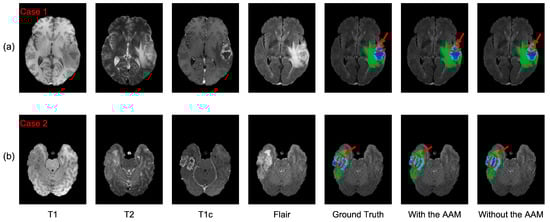

4.2.1. Analysis of the Axial Attention Mechanism

4.3. Analysis of the Bad Tumor Segmentation Results